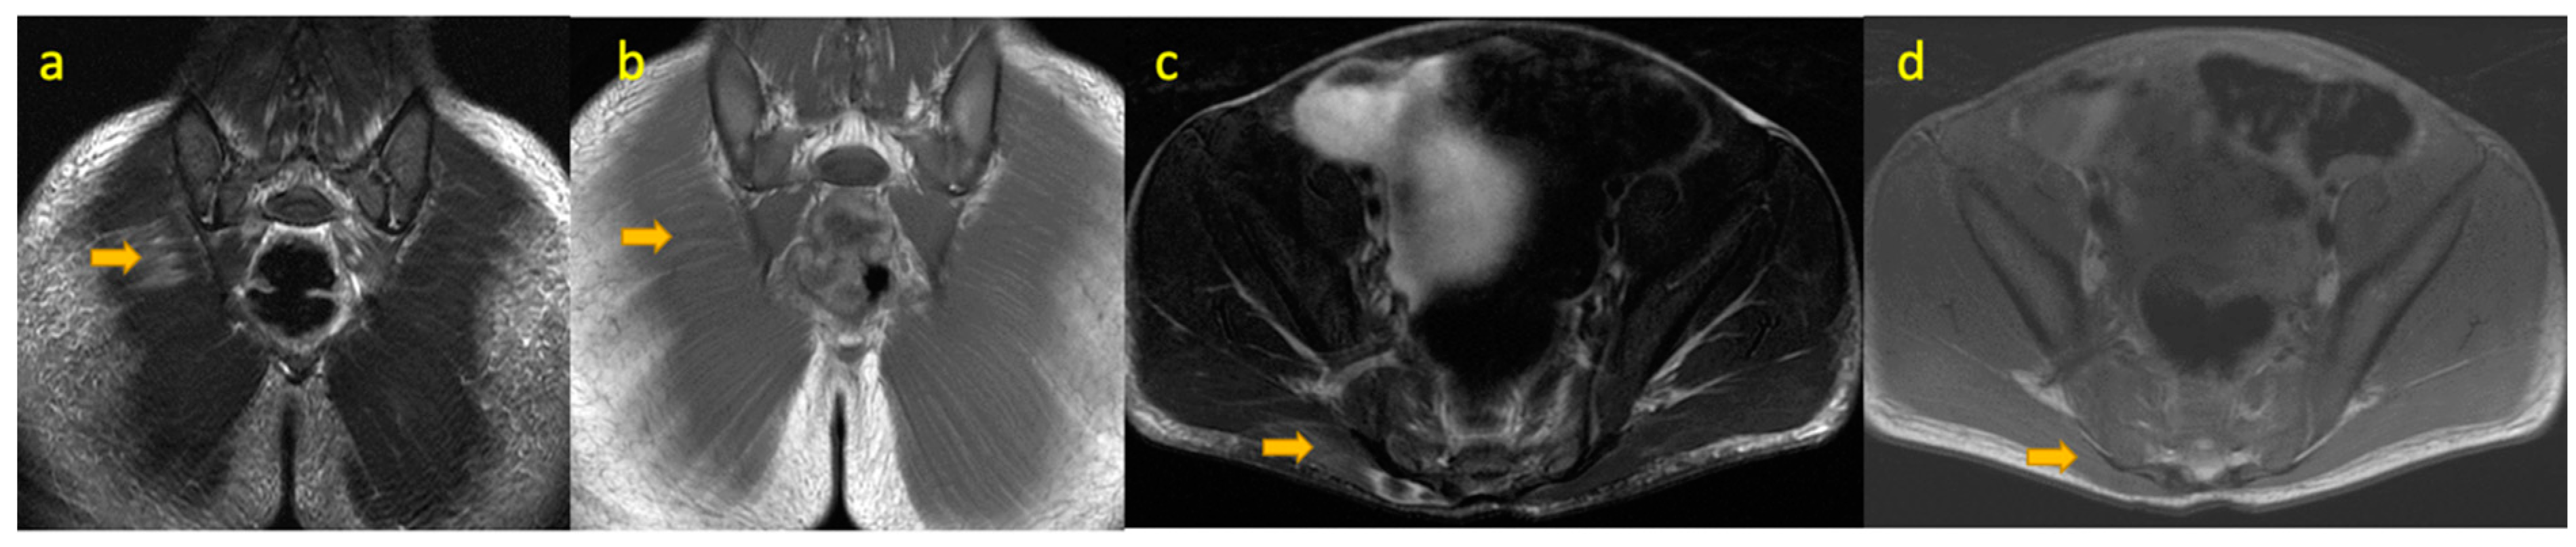

13. Septic Arthritis of the Sacroiliac Joint